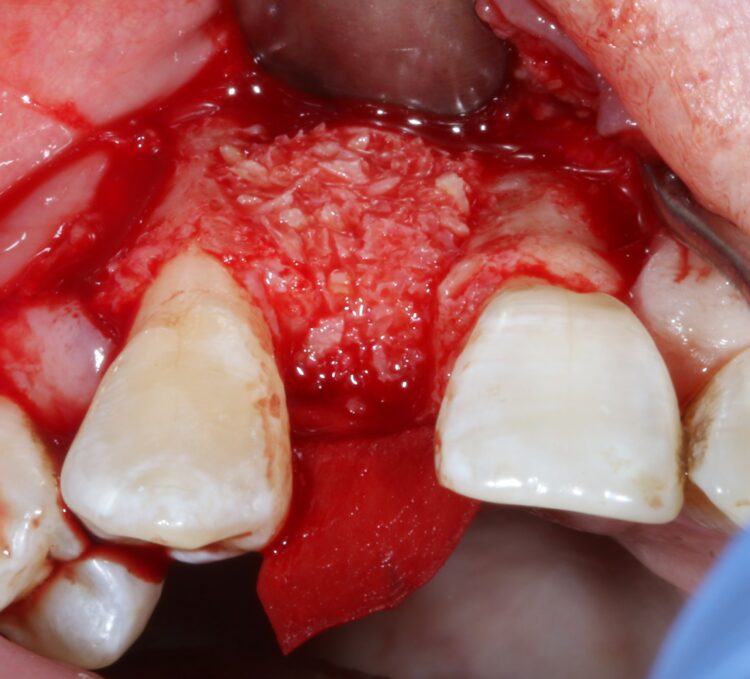

The first treatment phase included the elevation of a large full thickness flap to fully expose the area and enable the harvesting of autogenous bone utilising a safescraper.

The UR2 was then removed including excavation of all granulation tissue, taking care to avoid any direct curettage of the exposed UR3 root. The large bone defect was then filled with a 50/50 mix of autogenous bone chips and an allograft (MinerOss®, a cortico-cancellous mix – BioHorizons Camlog) and the buccal defect was covered with a native porcine collagen membrane with a high percentage of collagen type III for a prolonged barrier function of six months. No fixation pins were used.

The concept was that this exposed membrane would provide a barrier and prevent loss of the bone graft, but would also break down rapidly, favouring early epithelialisation of the open wound by secondary intention healing.

The occlusal aspect of the bone graft – which would remain exposed during the healing period – was covered with a shorter acting native collagen membrane. The concept was that this exposed membrane would provide a barrier and prevent loss of the bone graft, but would also break down rapidly, favouring early epithelialisation of the open wound by secondary intention healing.

The muco-periosteal flap was sutured back with 6.0 Prolene and no attempt was made to coronally advance the flap for complete closure. The rationale was to maintain the open socket wound and thereby preserve the original mucogingival relationship with no alteration. The socket entrance was sealed with the short acting membrane, while the original tooth (after root removal) was utilised as a temporary pontic and bonded to the adjacent teeth with flowable composite.